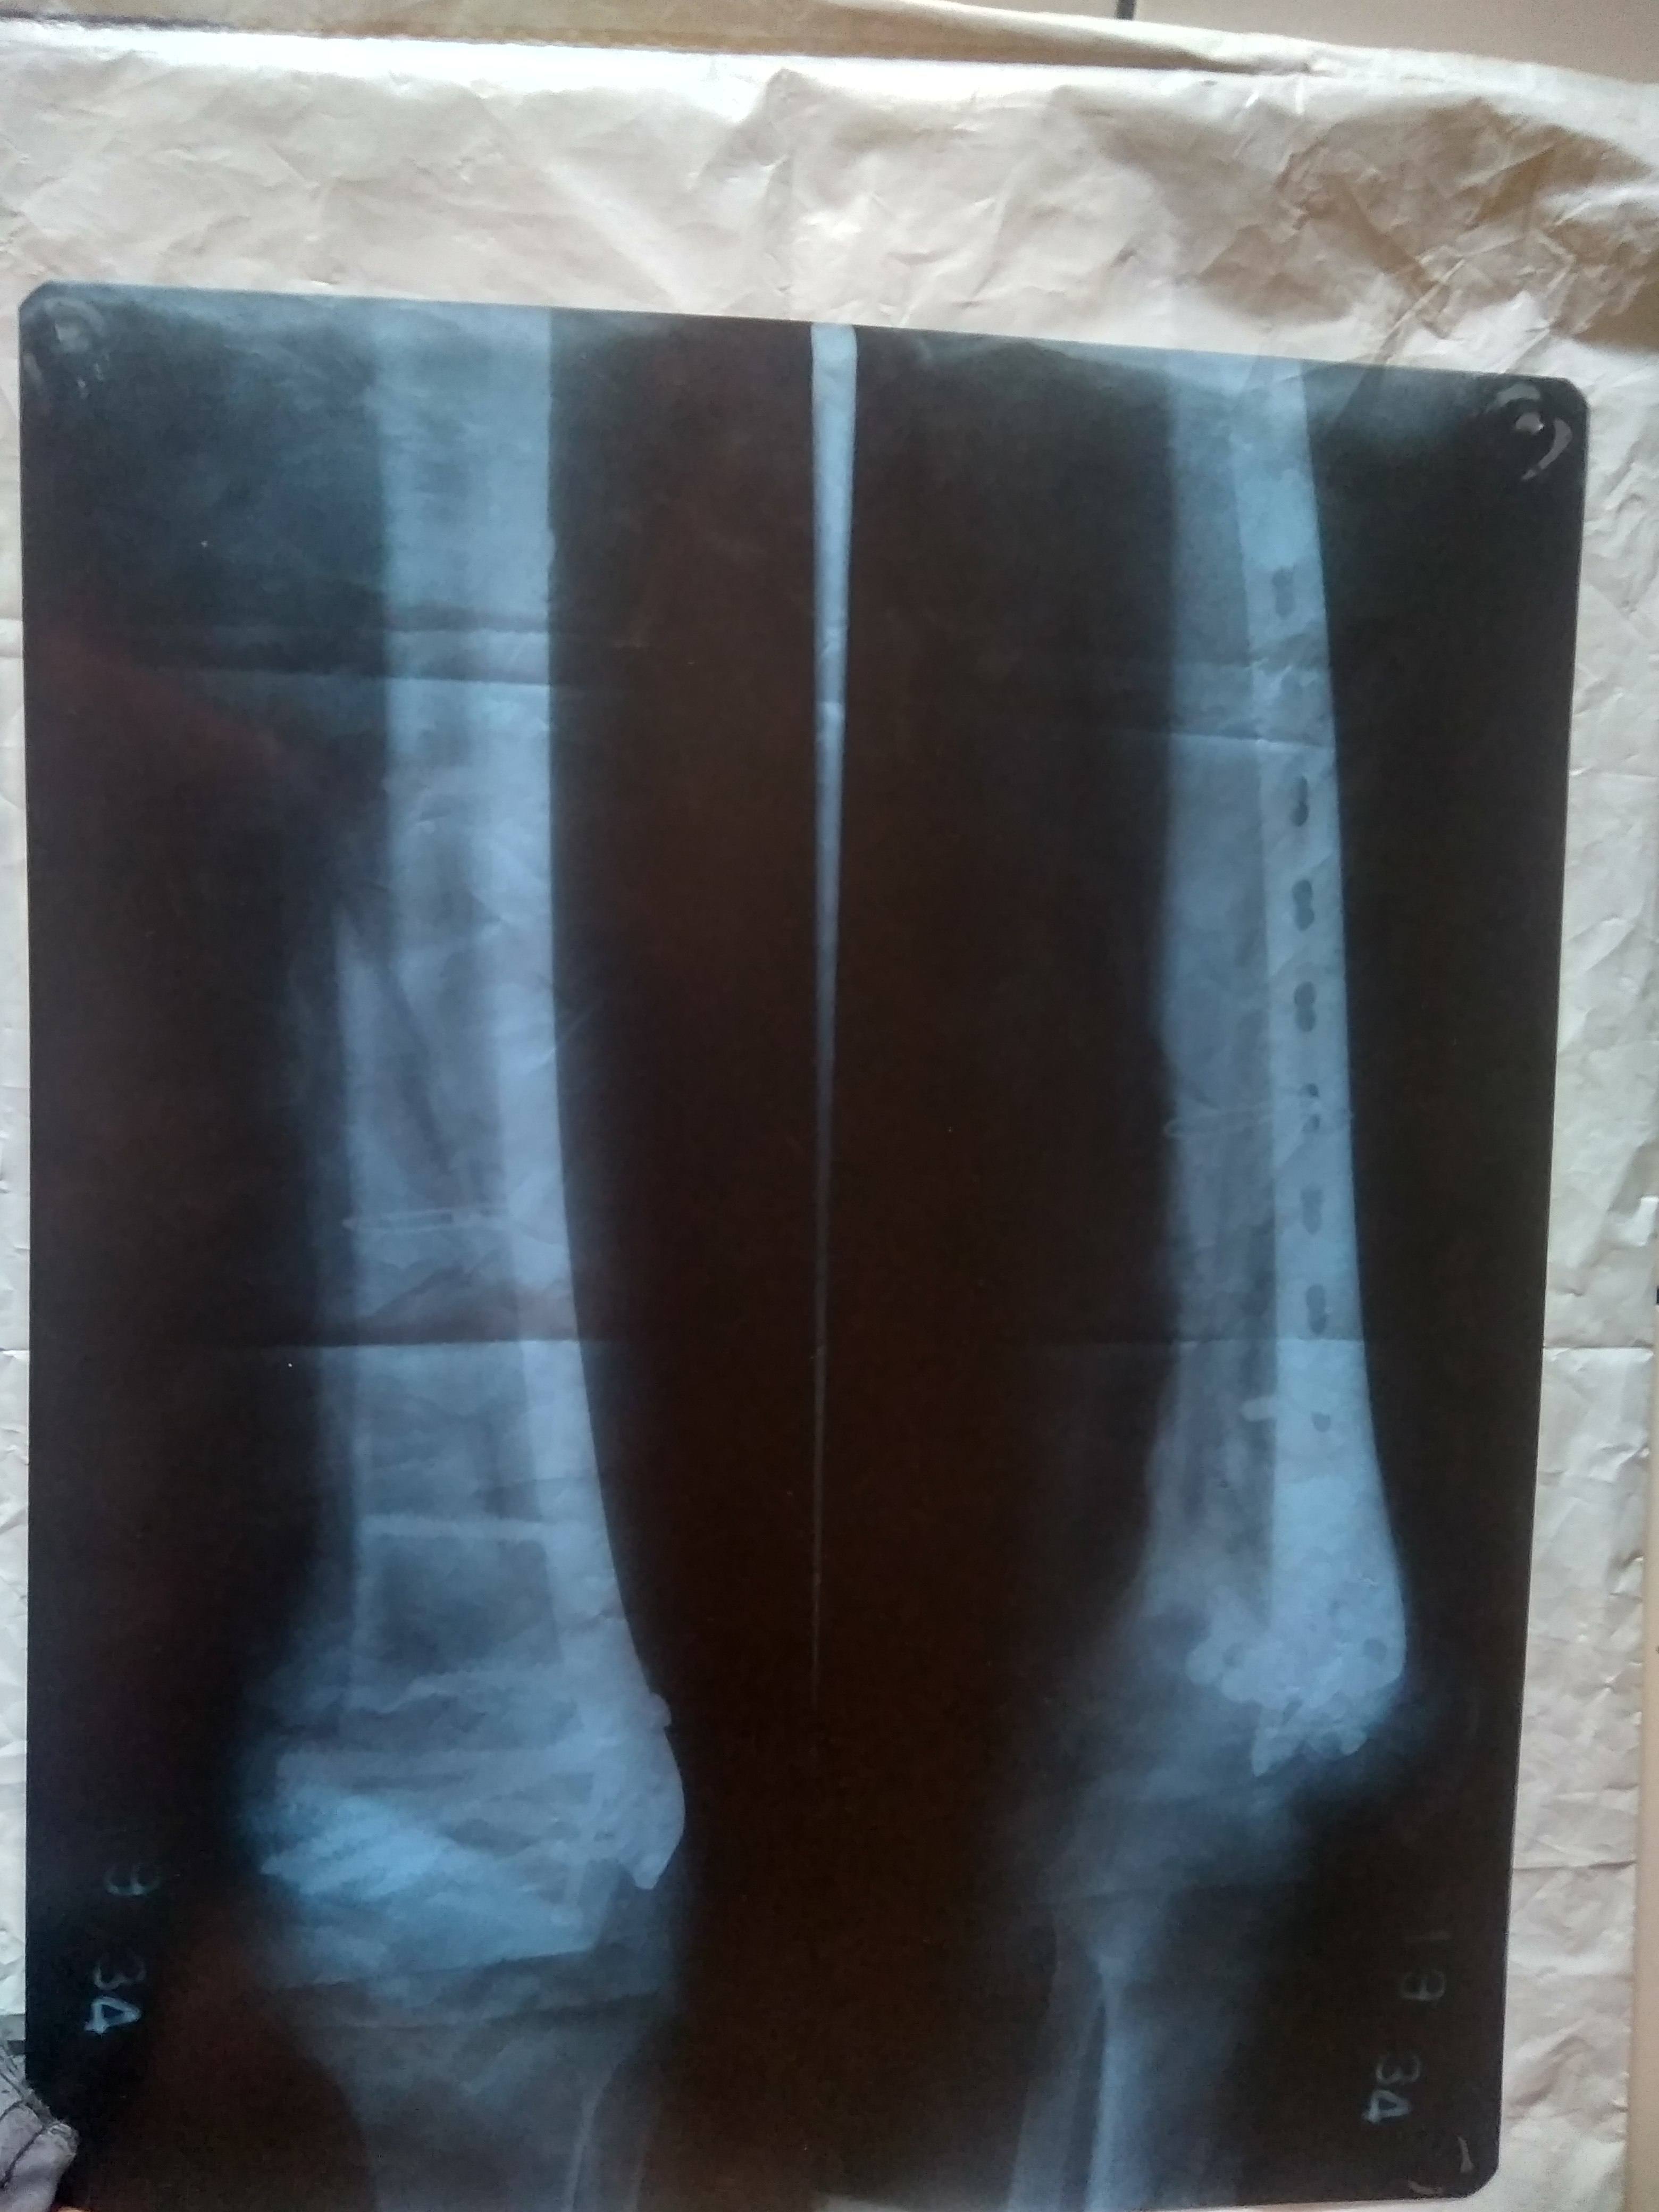

Bhaveshh Rathod